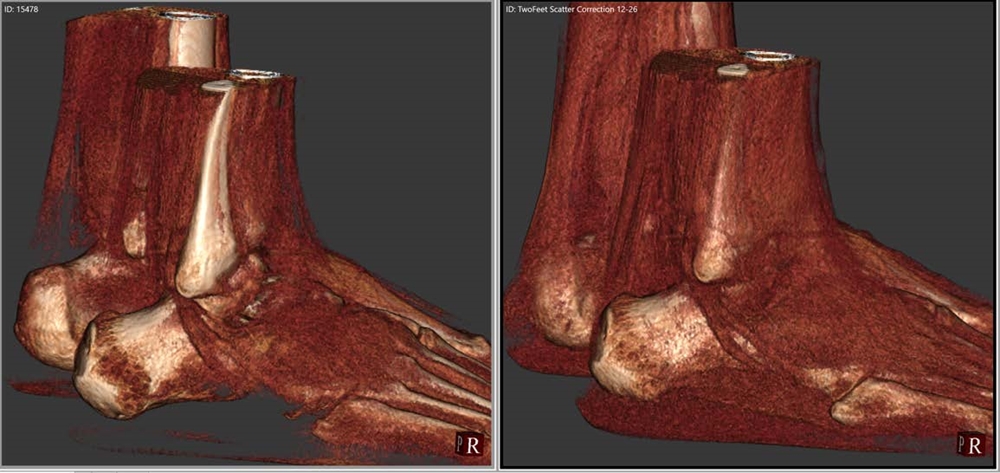

3D rendered image of bilateral feet

IBEX Trueview® (right) significantly enhances soft tissue visualisation, including authenticity and continuity of certain ligaments/tendons